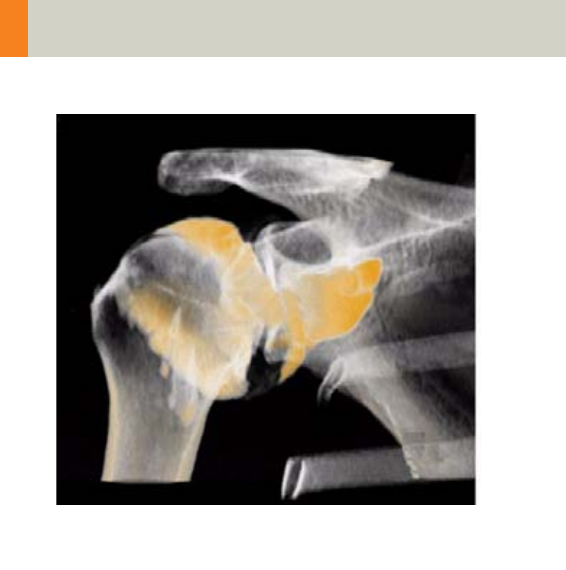

Shoulder 218

•Overview 218

- General Hints 219

- Body Kernels 219

•Scan Protocols 220

- Shoulder 220

- ShoulderVol 224